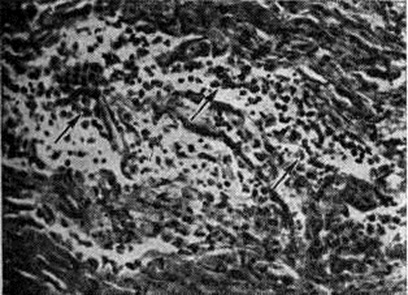

Воспалительную инфильтрацию, по их мнению, следует рассматривать как реактивный процесс на первичные изменения в миелиновой оболочке. Миелинотоксические факторы вызывают разрушение миелина в органотипических культурах ткани периферической нервной системы и имеют диагностическое значение. Эта модель используется для изучения иммунологический реакций замедленного и немедленного типа в развитии экспериментального аллергического Полиневрит Введение животным в инкубационном периоде заболевания ряда препаратов (АКТГ, циклофосфамида, антилимфоцитарной сыворотки) подавляет развитие процесса. Лечебный действием обладает невритогенный основной белок миелина, используемый в смеси с неполным стимулятором Фрейнда. Патологическая анатомия. В патоморфологические отношении Полиневрит разделяют на паренхиматозные и интерстициальные. Среди паренхиматозных Полиневрит различают формы с преимущественным изменением миелина и леммоцитов (периаксональные Полиневрит) и формы с преобладанием поражения аксона (аксональные Полиневрит). Интерстициальные Полиневрит характеризуются изменениями в оболочках и сосудах периферических нервов. Формы с вовлечением корешков и спинномозговых ганглиев называют полирадикулоневритами. В зависимости от этиологии процесса патоморфологические картина имеет ряд отличий. При острых первичных Полиневрит инфекционно-аллергического генеза, клинически протекающих по типу восходящего паралича Ландри (смотри полный свод знаний: Ландри восходящий паралич) или синдрома Гийена — Барре — Штроля, наблюдается преимущественное поражение миелиновых оболочек. На ранних стадиях этих заболеваний наблюдается скопление мононуклеаров вблизи миелиновых оболочек, которые подвергаются распаду. Одновременно происходит пролиферация леммоцитов, и их число увеличивается в 8—14 раз. Миелиновые оболочки набухают, приобретают сотовидное строение, происходит образование миелиновых шаров и местами — растворение миелина. В очагах демиелинизации, особенно расположенных перивенозно, формируются очаговые некрозы (рисунок 1) со скоплением макрофагов, содержащих жир. Воспалительные перивенозные и перикапиллярные инфильтраты состоят из лимфоидных клеток, полиморфных мононуклеаров, макрофагов (рисунок 2). Аксон увеличивается в размерах, происходит его лентовидное набухание, по ходу аксона формируются чёткообразные вздутия, наступают лизис волоконец и пролиферация леммоцитов (рисунок 3). Гибель нервных волокон приводит к развитию валлеровской дегенерации (смотри полный свод знаний: Валлера перерождение). Вследствие разрушения миелина эндоневральные промежутки сближены, а периневральные пространства расширены и инфильтрированы лимфоидными элементами. Воспалительный и демиелинизирующий процесс при первичных И. является обратимым. Ремиелинизация наступает на 2—3-й недель от начала болезни, как правило, сопровождается регенерацией нервных волокон. В редких случаях аксоны погибают и на их месте формируются коллагеновые фибриллы и аморфное вещество эндоневрия. При гиповитаминозных, диабетических, токсических, порфириновых, алкогольных Полиневрит наблюдается преимущественно аксональное поражение, которое сопровождается дегенерацией аксонов, пролиферацией леммоцитов, набуханием двигательных моторных концевых бляшек. В нервных волокнах прослеживаются различные стадии гибели аксонов, вплоть до полного их исчезновения. На месте погибших нервных волокон остаются беспорядочно расположенные волокна эндоневрия, макрофаги (рисунок 4). Одновременно с дегенерацией аксона можно проследить процессы регенерации, когда на месте погибших волокон происходит образование новых мелких волоконец. В поздних стадиях регенерации в миелиновых нервных волокнах отдельные аксоны достигают нормальной величины, большая часть их остаётся атрофичной. Аксональная невропатия сопровождается дегенерацией миелина, чаще в форме сегментарной демиелинизации. Такая смешанная патология объясняется вовлечением в процесс леммоцитов и нарушением процесса миелинообразования. При ультраструктурном исследовании нарушение метаболических процессов в аксонах проявляется истончением аксоплазматических органелл, вакуолизацией и редукцией диаметра аксона, скоплением гликогена в леммоцитах. Интерстициальные Полиневрит наблюдаются при общих инфекциях: вирусном гепатите, лепре, опоясывающем лишае (смотри полный свод знаний: Герпес) и другие, а также при артериитах, ревматоидных артритах, ишемии, амилоидозе и других заболеваниях. Патологический процесс при этом характеризуется увеличением эндоневрального коллагена с формированием воспалительных изменений в интерстициальной ткани периферических нервов. Отмечается умеренная пролиферация леммоцитов.